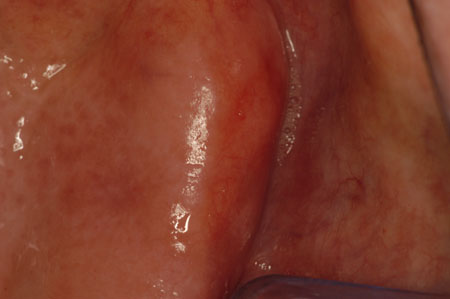

Potentially malignant oral mucosal lesions (oral pre-cancers) mainly include some leukoplakias and erythroplakia (also known as erythroleukoplakia). Erythroplakia, though much less common than leukoplakias, has higher malignant potential. Erythroplakia presents as a velvety red plaque, and at least 85% of cases show frank malignancy or severe epithelial dysplasia.[66]Quah SR, Cockerham WC, eds. International encyclopedia of public health. 2nd ed. Oxford: Elsevier; 2017. Leukoplakia, particularly where admixed with red lesions (speckled leukoplakia), is potentially malignant. By utilising a binary microscopic classification system, where lesions were classified as low-risk dysplasia or high-risk dysplasia, the latter was a significant indicator for evaluating malignant transformation.[67]Liu W, Wang YF, Zhou HW, et al. Malignant transformation of oral leukoplakia: a retrospective cohort study of 218 Chinese patients. BMC Cancer. 2010 Dec 16;10:685.

[Figure caption and citation for the preceding image starts]: ErythroplakiaCourtesy of Dr James Sciubba; used with permission [Citation ends].

[Figure caption and citation for the preceding image starts]: Speckled leukoplakiaCourtesy of Dr James Sciubba; used with permission [Citation ends].

[Figure caption and citation for the preceding image starts]: Proliferative verrucous leukoplakiaCourtesy of Dr James Sciubba; used with permission [Citation ends].

[Figure caption and citation for the preceding image starts]: Sublingual leukoplakiaCourtesy of Dr James Sciubba; used with permission [Citation ends].

[Figure caption and citation for the preceding image starts]: Candidal leukoplakiaCourtesy of Dr James Sciubba; used with permission [Citation ends].